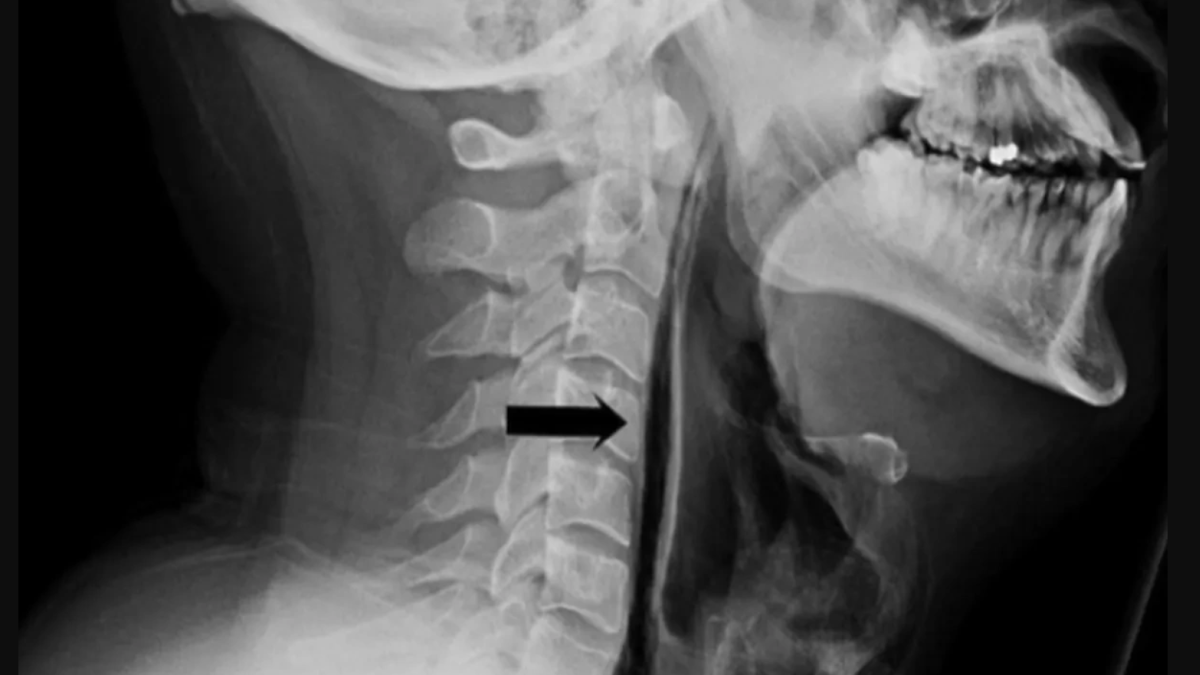

Ранее в соцсетях появилась информация о том, что 34-летний пациент ЦРБ города Суоярви получил разрыв пищевода, пытаясь сдержать чихание. Позднее выяснилось, что случай произошёл в Великобритании в 2018 году. Новость и снимки были взяты из «Британского медицинского журнала». Больница Карелии удалила пост с ними после того, как информация разошлась по федеральным порталам.

Фото Британский медицинский журнал